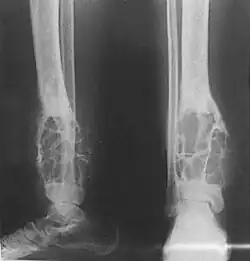

Histologically, islands of epithelial cells are found in a fibrous stroma. The tumor is typically well-demarcated, osteolytic and eccentric, with cystic zones resembling soap bubbles.[2]

X-rays of the affected area show a well defined tumour in bone, with multiple lobules giving a "soap bubble" appearance.[9] MRI can provide a more useful guide to its severity.[9]